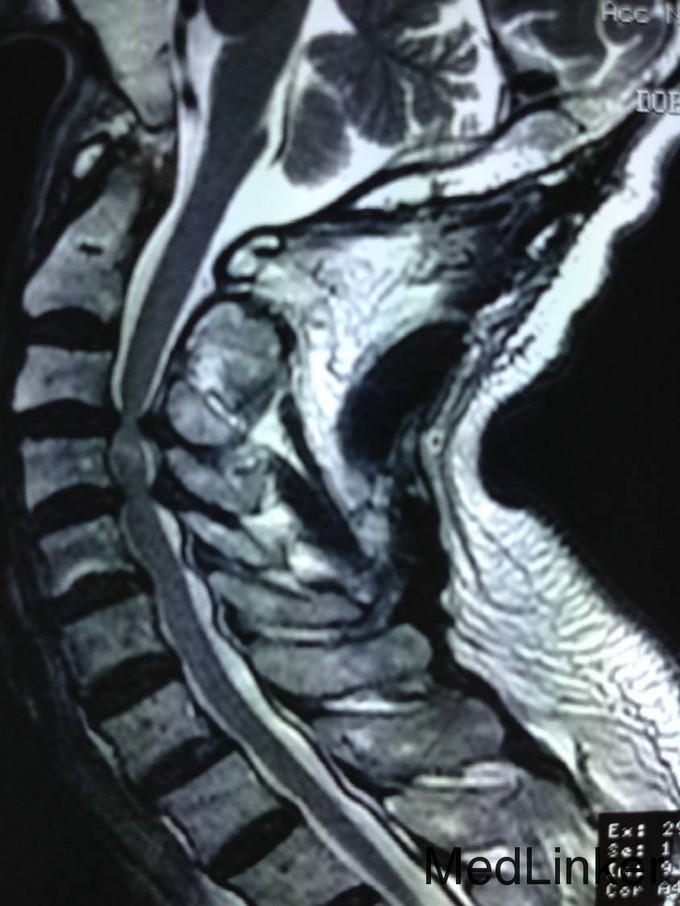

患者男,81岁,自述于1个月前出现双上肢感觉减退,发胀,以左侧为重,后来加重,左侧握力减退,于201医院就诊,行颈椎MR检查,提示为颈3-4、4-5间盘突出,为求进一步治疗就诊于我院,患者病来饮食、睡眠佳。大小便正常,体重无明显变化。

颈椎生理弯曲消失,活动度正常。双上肢感觉减退。双手握力(R5级,L4级),伸肘肌力(R5级,L5级),屈肘肌力(R5级,L5级),Hoffman(R-,L+)桡动脉搏动有力,末梢血运良。

诊断:颈椎病,颈椎间突出,高血压病 患者入院后完善相关检查,请相关科室及麻醉科会诊,医院医务部审批后,查无其他手术禁忌症,于全麻下行颈椎后路单开门椎管扩大减压侧块螺钉内固定术。术后给予患肢雾化祛痰,抗炎,消肿,营养神经,接骨等对症治疗。术后患者在颈领的保护下可下地行走,术后14天拆线后予以出院,